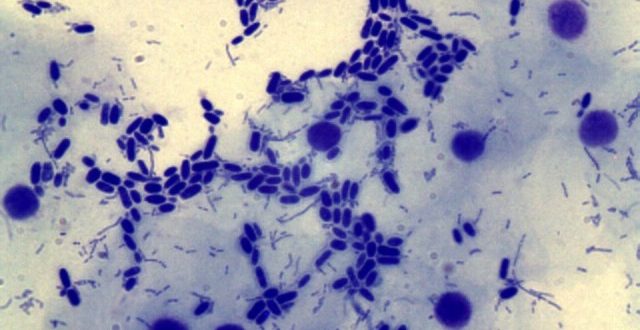

Мицелий гриба в мазке. НЕ КАНДИДА

КАНДИДОЗ: Простой способ проверить наличие грибка в организме Очень важно вовремя проверять себя на кандидоз, чтобы понять, не является ли грибок причиной ваших проблем со здоровьем. Грибок кандида…